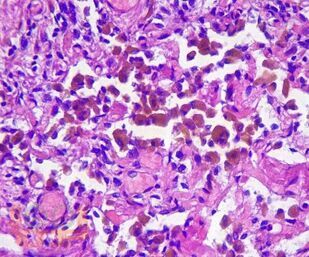

В учебном пособии представлен теоретический материал, перечень макропрепаратов и микропрепаратов, демонстрирующих типовые проявления патологических процессов. В цветных иллюстрациях и в описании микропрепаратов сделан акцент на наиболее важных гистологических изменениях, позволяющих на светооптическом уровне диагностировать и дифференцировать состояния, отклоняющиеся от нормы, в том числе с использованием различных гистологических окрасок. Пособие помогает выделить главные аспекты изучаемых патологических процессов, организовать и конкретизировать учебный процесс.